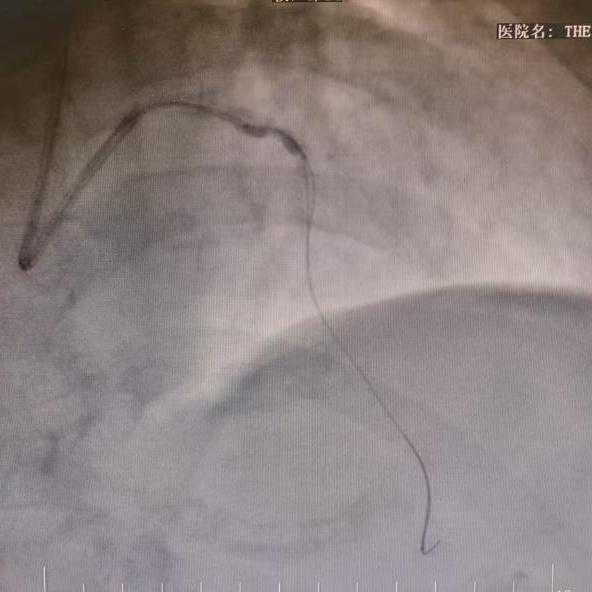

手术第一步, 首先使用普通球囊无法扩张钙化病变,随后使用直径仅有1.5毫米的钻石磨头(旋磨头),以每分钟近16万转的速度,对血管内的钙化斑块进行精准旋磨。这只高速旋转的“金刚钻”小心翼翼地研磨、粉碎了最表层的坚硬钙化,为后续治疗开辟了一条初步通道。

普通球囊无法扩张病变

冠状动脉旋磨术